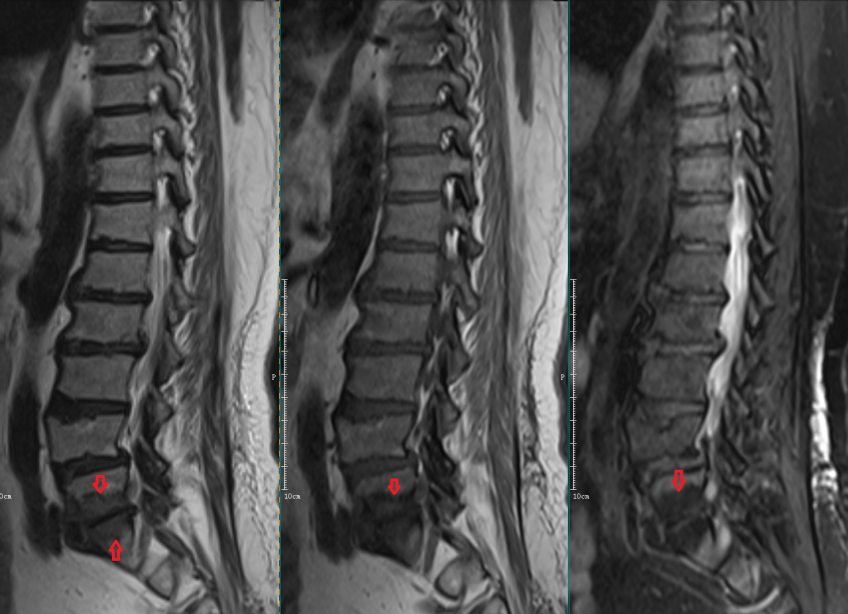

Modic Ⅱ型:

L4-5椎间盘上下缘见条带状异常信号,T1WI高信号,T2WI高信号,STIR序列低信号。

L5-S1椎间盘上下缘见条带状异常信号,T1WI高信号,T2WI高信号,STIR序列低信号。

Modic Ⅲ型:

L5-S1椎间盘上下缘见条带状异常信号,T1WI、T2WI及STIR序列均呈低信号。